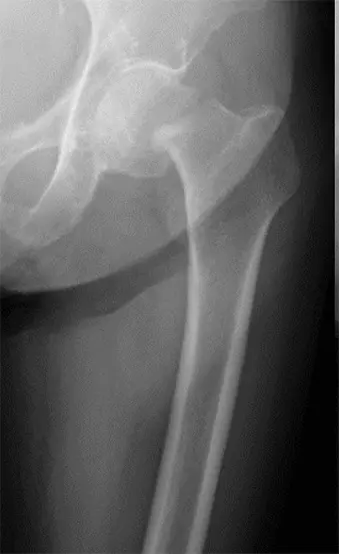

人工骨頭置換術における下双子筋近位の 外旋筋群温存後方アプローチについて

大腿骨頚部骨折に対する人工骨頭置換術後の骨頭脱臼は、一度脱臼すると再脱臼を繰り返し治療に難渋する。しかしながら大腿骨頚部骨折は高齢者での発生率が高いため、認知症を合併していることが多く、術後脱臼肢位の指導が困難であることが少なくない。今回、術後の後方脱臼リスクを軽減するため、下双子筋より近位の外旋筋群を温存する後方アプローチと外閉鎖筋・関節包の修復を行う術式を経験したので報告する。

画像所見

単純X線検査にて右大腿骨頸部骨折の所見(AO分類 31B)を認めた。

側臥位にて骨板固定器にて体位を固定し、股関節後方アプローチを施行。大腿方形筋近位を1/3~1/2程度切離し、下双子筋と大腿方形筋間を確認したうえ、下双子筋より近位の外旋筋群(下双子筋、内閉鎖筋、上双子筋および梨状筋)を近位へレトラクトする。外閉鎖筋を切離し、下双子筋よりやや近位で下双子筋と平行に関節包、坐骨大腿靭帯を切開する。関節包、坐骨大腿靭帯を切開した後に骨頭を抜去し、骨幹部を小転子より1横指近位で骨切りし髄腔をラスピングしたうえで、人工骨頭トライアルならびにインプラント(Cup 44mm, Stem size6, Neck +3mm)を挿入。試験整復を行い、屈曲60度・内旋90度で脱臼せず、90度 内旋90度で脱臼しない事を確認。創内を十分に洗浄後、外閉鎖筋腱と関節包をファイバーワイヤーにて大腿骨に強固に縫合し、閉創。

術後2日目より車椅子移乗訓練を開始。右下肢は僅かに拳上可能でステップには至らず解除要す状態であったが、術後4日目からはステップ可能、平行棒内歩行訓練も疼痛自制内で可能。術後4か月の現在、全荷重歩行中で脱臼も認めていない。